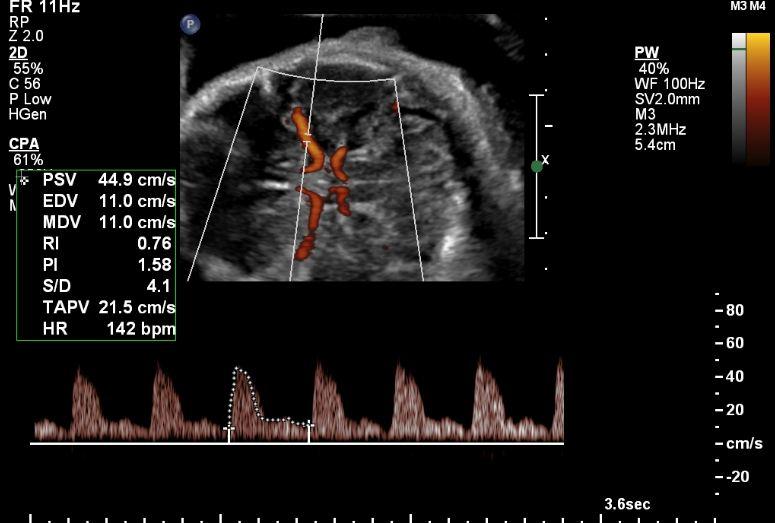

This course provides an in-depth exploration of Multi-Vessel Doppler Studies in Intra-Uterine Growth Restriction (IUGR). Learn the essential Doppler techniques to assess fetal health, identify risks, and understand the progression of IUGR. Gain valuable knowledge on umbilical artery, middle cerebral artery, ductus venosus, and umbilical vein Doppler evaluations for improved diagnosis and management.

Identify Doppler wave patterns associated with IUGR.